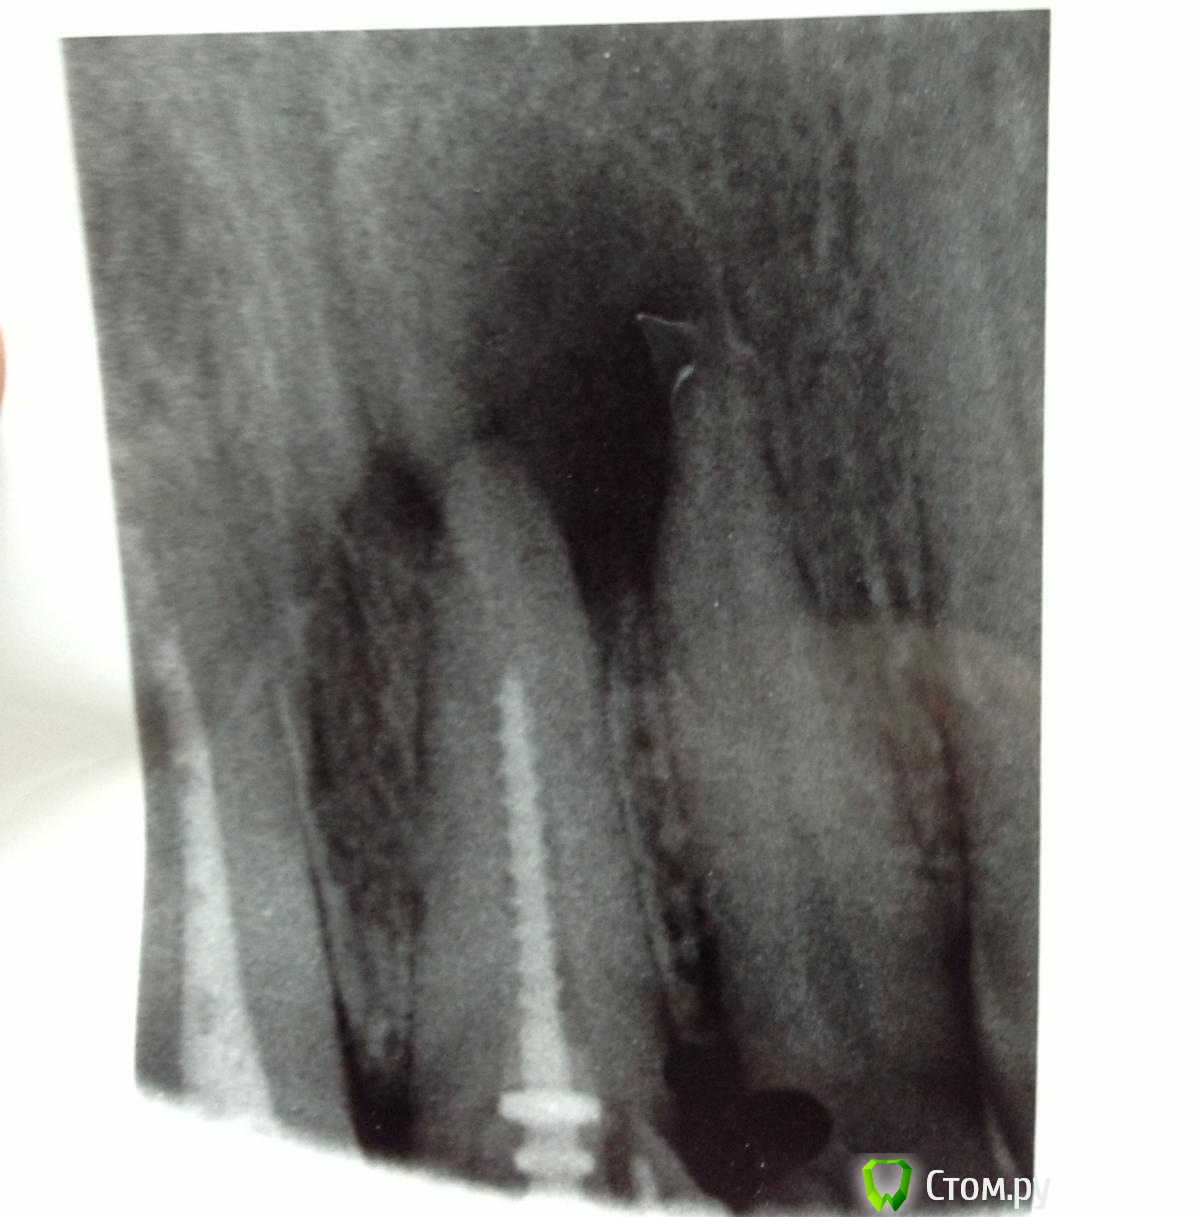

SSTi Опубликовано 2 июня, 2014 Автор Поделиться Опубликовано 2 июня, 2014 (изменено) Пришел парень с 36. Зуб болел при накусывании, прикасаться языком также было больно. Раньше лечен по поводу осложненного кариеса(пульпит). Пару дней назад ему убрали пломбу чуть прошли каналы и поставили времянку. Ему стало немного лучше. Сегодня пришел ко мне. Я делаю снимок, а там.....Анестезия, коффер, убираю времянку и из медиальных фонтанчиком получаю гной(никакого отека по переходной нет!). Прохожу щечный без проблем до f1, дистальный до f2, язычный то ли со ступенькой, то ли еще что то, но файл дальше 5 мм не шел. Потом десяткой взял чуть ближе к щечному и прошел. Очень долго мылись( 5 шприцев гипохлорита ) , гной подтекал минут 20. Уз. Эдта. Хлоргексидин. Кальций. Будем наблюдать пока....Снимки с файлами Изменено 2 июня, 2014 пользователем SSTi Ссылка на комментарий

Kivilgar Опубликовано 2 июня, 2014 Поделиться Опубликовано 2 июня, 2014 (изменено) Зуп покойник, эво как там расковыряли сильно устьевую треть каналаПервая фотка не грузится((( Чего там с фуркацией? Изменено 2 июня, 2014 пользователем Kivilgar Ссылка на комментарий

SSTi Опубликовано 2 июня, 2014 Автор Поделиться Опубликовано 2 июня, 2014 да видел я.... причем было запломбировано в дистальном только в расковыренной трети. Ссылка на комментарий

SSTi Опубликовано 2 июня, 2014 Автор Поделиться Опубликовано 2 июня, 2014 Чего там с фуркацией? с фуркацией ин рото все терпимо. перфо нет никаких Ссылка на комментарий

FoXx^_^ Опубликовано 2 июня, 2014 Поделиться Опубликовано 2 июня, 2014 А по первому снимку как-будто перфо по фуруации ближе к медиальным! Ссылка на комментарий

SSTi Опубликовано 2 июня, 2014 Автор Поделиться Опубликовано 2 июня, 2014 Это на снимке так. Я контрастность прибавил. Во рту нет перфо. Было бы-не стал бы браться Ссылка на комментарий

SSTi Опубликовано 2 июня, 2014 Автор Поделиться Опубликовано 2 июня, 2014 Меня больше волнует что делать дальше. Здесь нужна вкладка по-хорошему и коронка. Идеально конечно , если бы косточка подросла и имплантация. Ссылка на комментарий